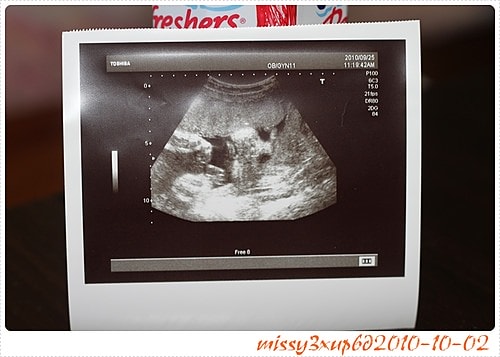

玳瑁要乖乖呀,媽咪是希望你可以待到38W捏,不要讓肚子練習太快呀。 基於上次的產檢師不夠認真,這次祈禱了一下,果然遇到比較仔細認真的產檢師,可是玳瑁不乖呀,表情看不到。 可…

應該說大醫院設備太好了吧,哈哈,當初別說看桓的表情,一點記憶點有什麼都不知道,只知道桓那時候很大辣辣的十五周就開獎了= =。 就是腳開開那種!!! 所以玳瑁在孕期中,超…

這次去馬偕其實是21W了,我才知道原來例行性超音波,會照的這麼仔細喔? 會看一下手呀,腳呀,肚子頭圍,我其實很囧,因為桓兒根本沒有這樣仔細看過。 這叫做傻傻生傻傻沒事嗎? …